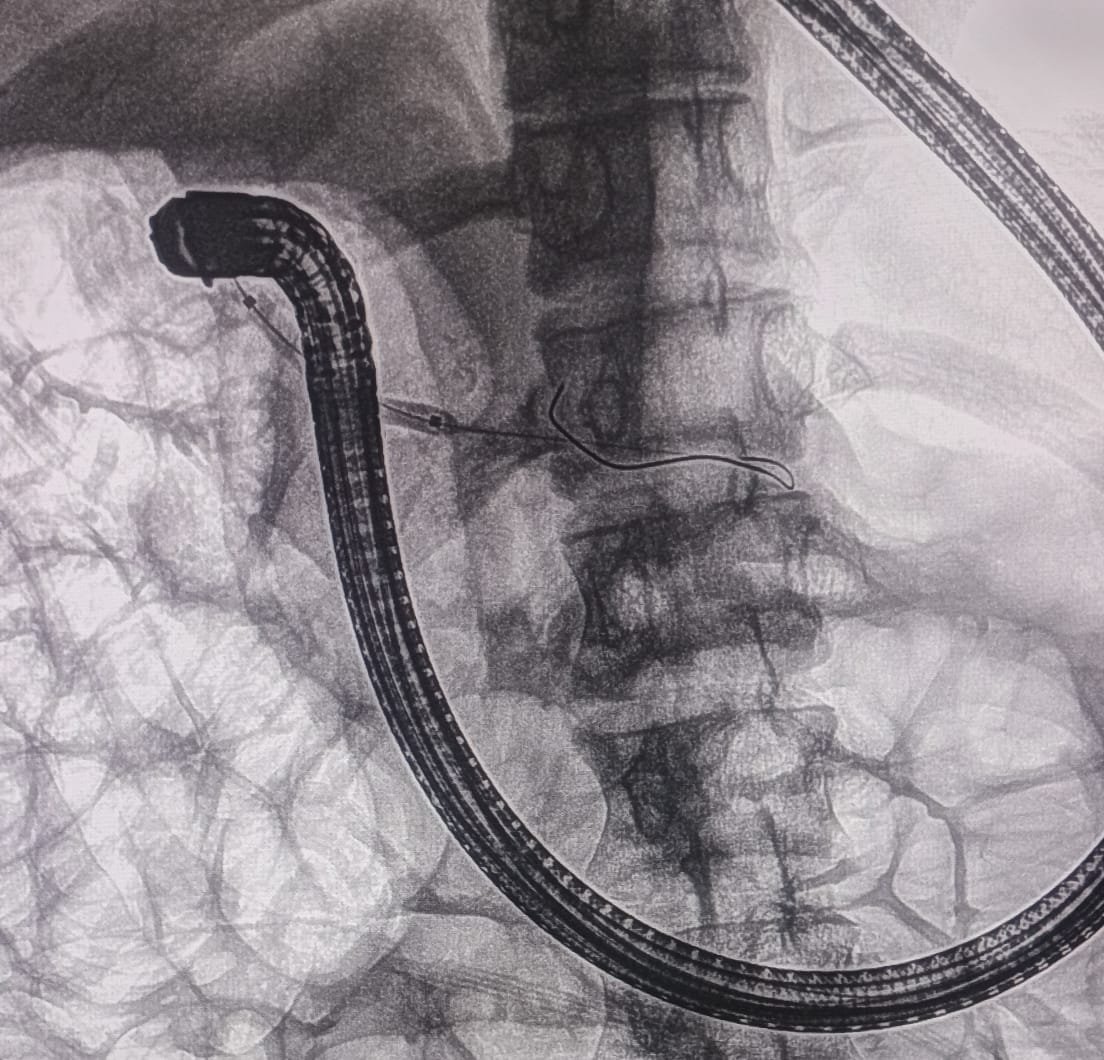

Chronic Pancreatitis ERCP Image 3

Balloon Dilation

Communication of duct of Santorini was found to be of very small caliber. Cannula was passed into the pancreatic duct of body and tail. Duct of Santorini was dilated up to 4mm with biliary hurricane balloon. A 7Fr x 7cm single pigtail pancreatic stent was placed in the PD.